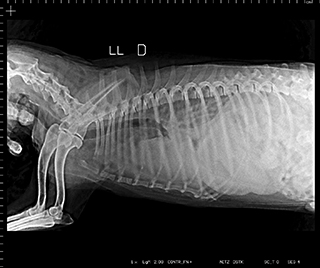

Radiologia Digital Direta / Digital Radiography

As radiografias geradas digitalmente podem ser transmitidas para iPad Apple®, notebooks e smartphones.

iPad com tela Retina Apple® possibilita a visualização das imagens com maior qualidade diagnóstica.